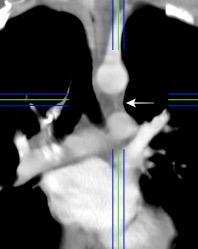

Anatomía

BPI: 75% de normales

La imagen es probable que represente al BPI, a la altura del nacimiento del BLSI.

AV,. The left lateral radiograph of the chest. Part One. Med. Radiogr. Photogr.1979.

La presencia de tumor o ganglios rodeando el BPI hace que este aparezca como mucho más nítido y definido.

Carcinoma microcítico..

Parálisis frénica. Atelectasia parcial de LSI.

Whitten CR. A Diagnostic Approach to Mediastinal Abnormalities. Radiographics 2007 / Marano R et al. Cardiac Silhouette findings And mediastinal lines and stripes. Chest. 2011